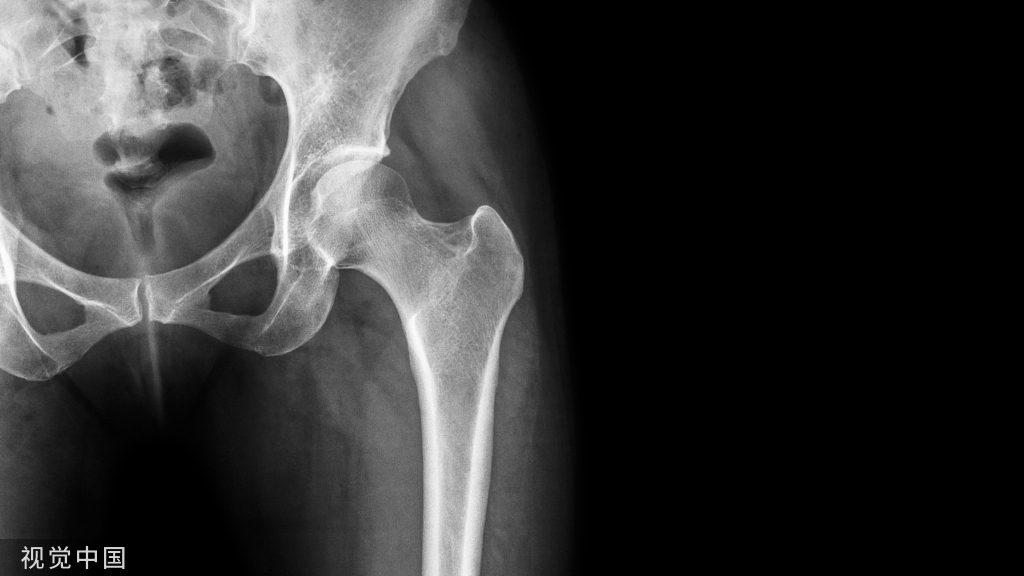

22、克氏针取出非骨水泥型股骨柄

埃及的Mahmoud A. Hafez医生等介绍一种利用克氏针即可取出非骨水泥型假体的方法,术中无需截骨。

使用不同尺寸的克氏针(1.0-1.8mm)插入假体-骨界面的周围。通过用克氏针沿着股骨假体的全长,在股骨假体-骨界面的周围建立出间隙,从而达到“松动”假体的目的。首先用直径小的克氏针制造出小间隙,随后再用直径更大一点的克氏针,再在股骨解剖轴线上往回敲假体。

作者总结经验:1.不推荐一次性置入全长的克氏针,而是先在一定深度的假体-骨界面周围依次建立间隙,再向假体的尾部置入;2.每次只使用一枚克氏针,避免克氏针断裂和遗留在髓腔。